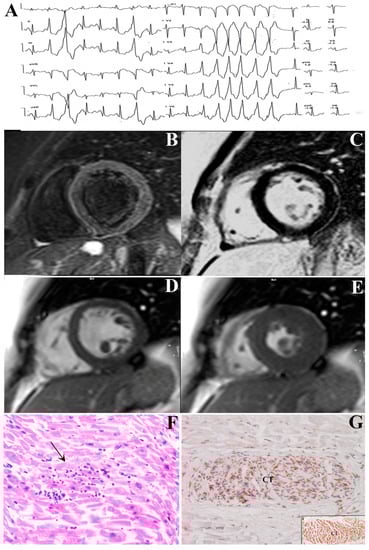

Inflammation of Conduction Tissue in Patients with Arrhythmic Phenotype of Myocarditis

4.1. Clinical Studies

4.2. Endomyocardial Biopsy Studies